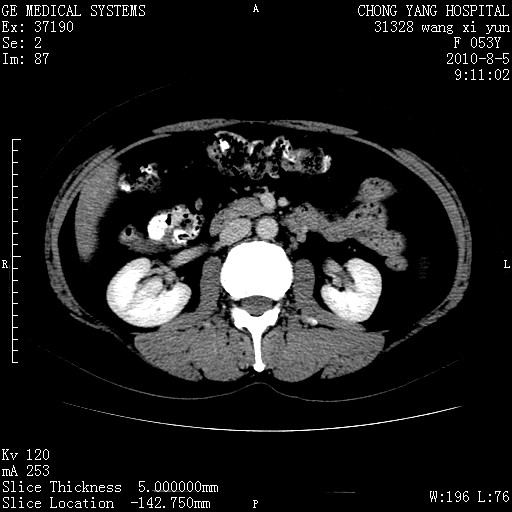

标题: CT28214:F41Y 血尿二十天,建议盆腔平扫加增强。

1)考虑肝左叶胆管细胞癌。2)脂肪肝。